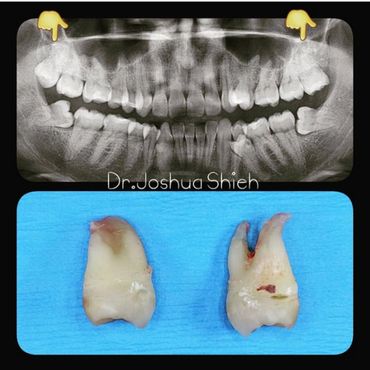

If the tooth is planned for extraction, an x-ray of the area will be taken to plan for the type of extraction.

Simple extractions are performed on erupted teeth that have regular anatomy (root and crown), and are not severely broken.

If you feel that your wisdom teeth are starting to cause problems, book an appointment to assess their condition, a panoramic x-ray will be taken and a thorough examination is conducted.